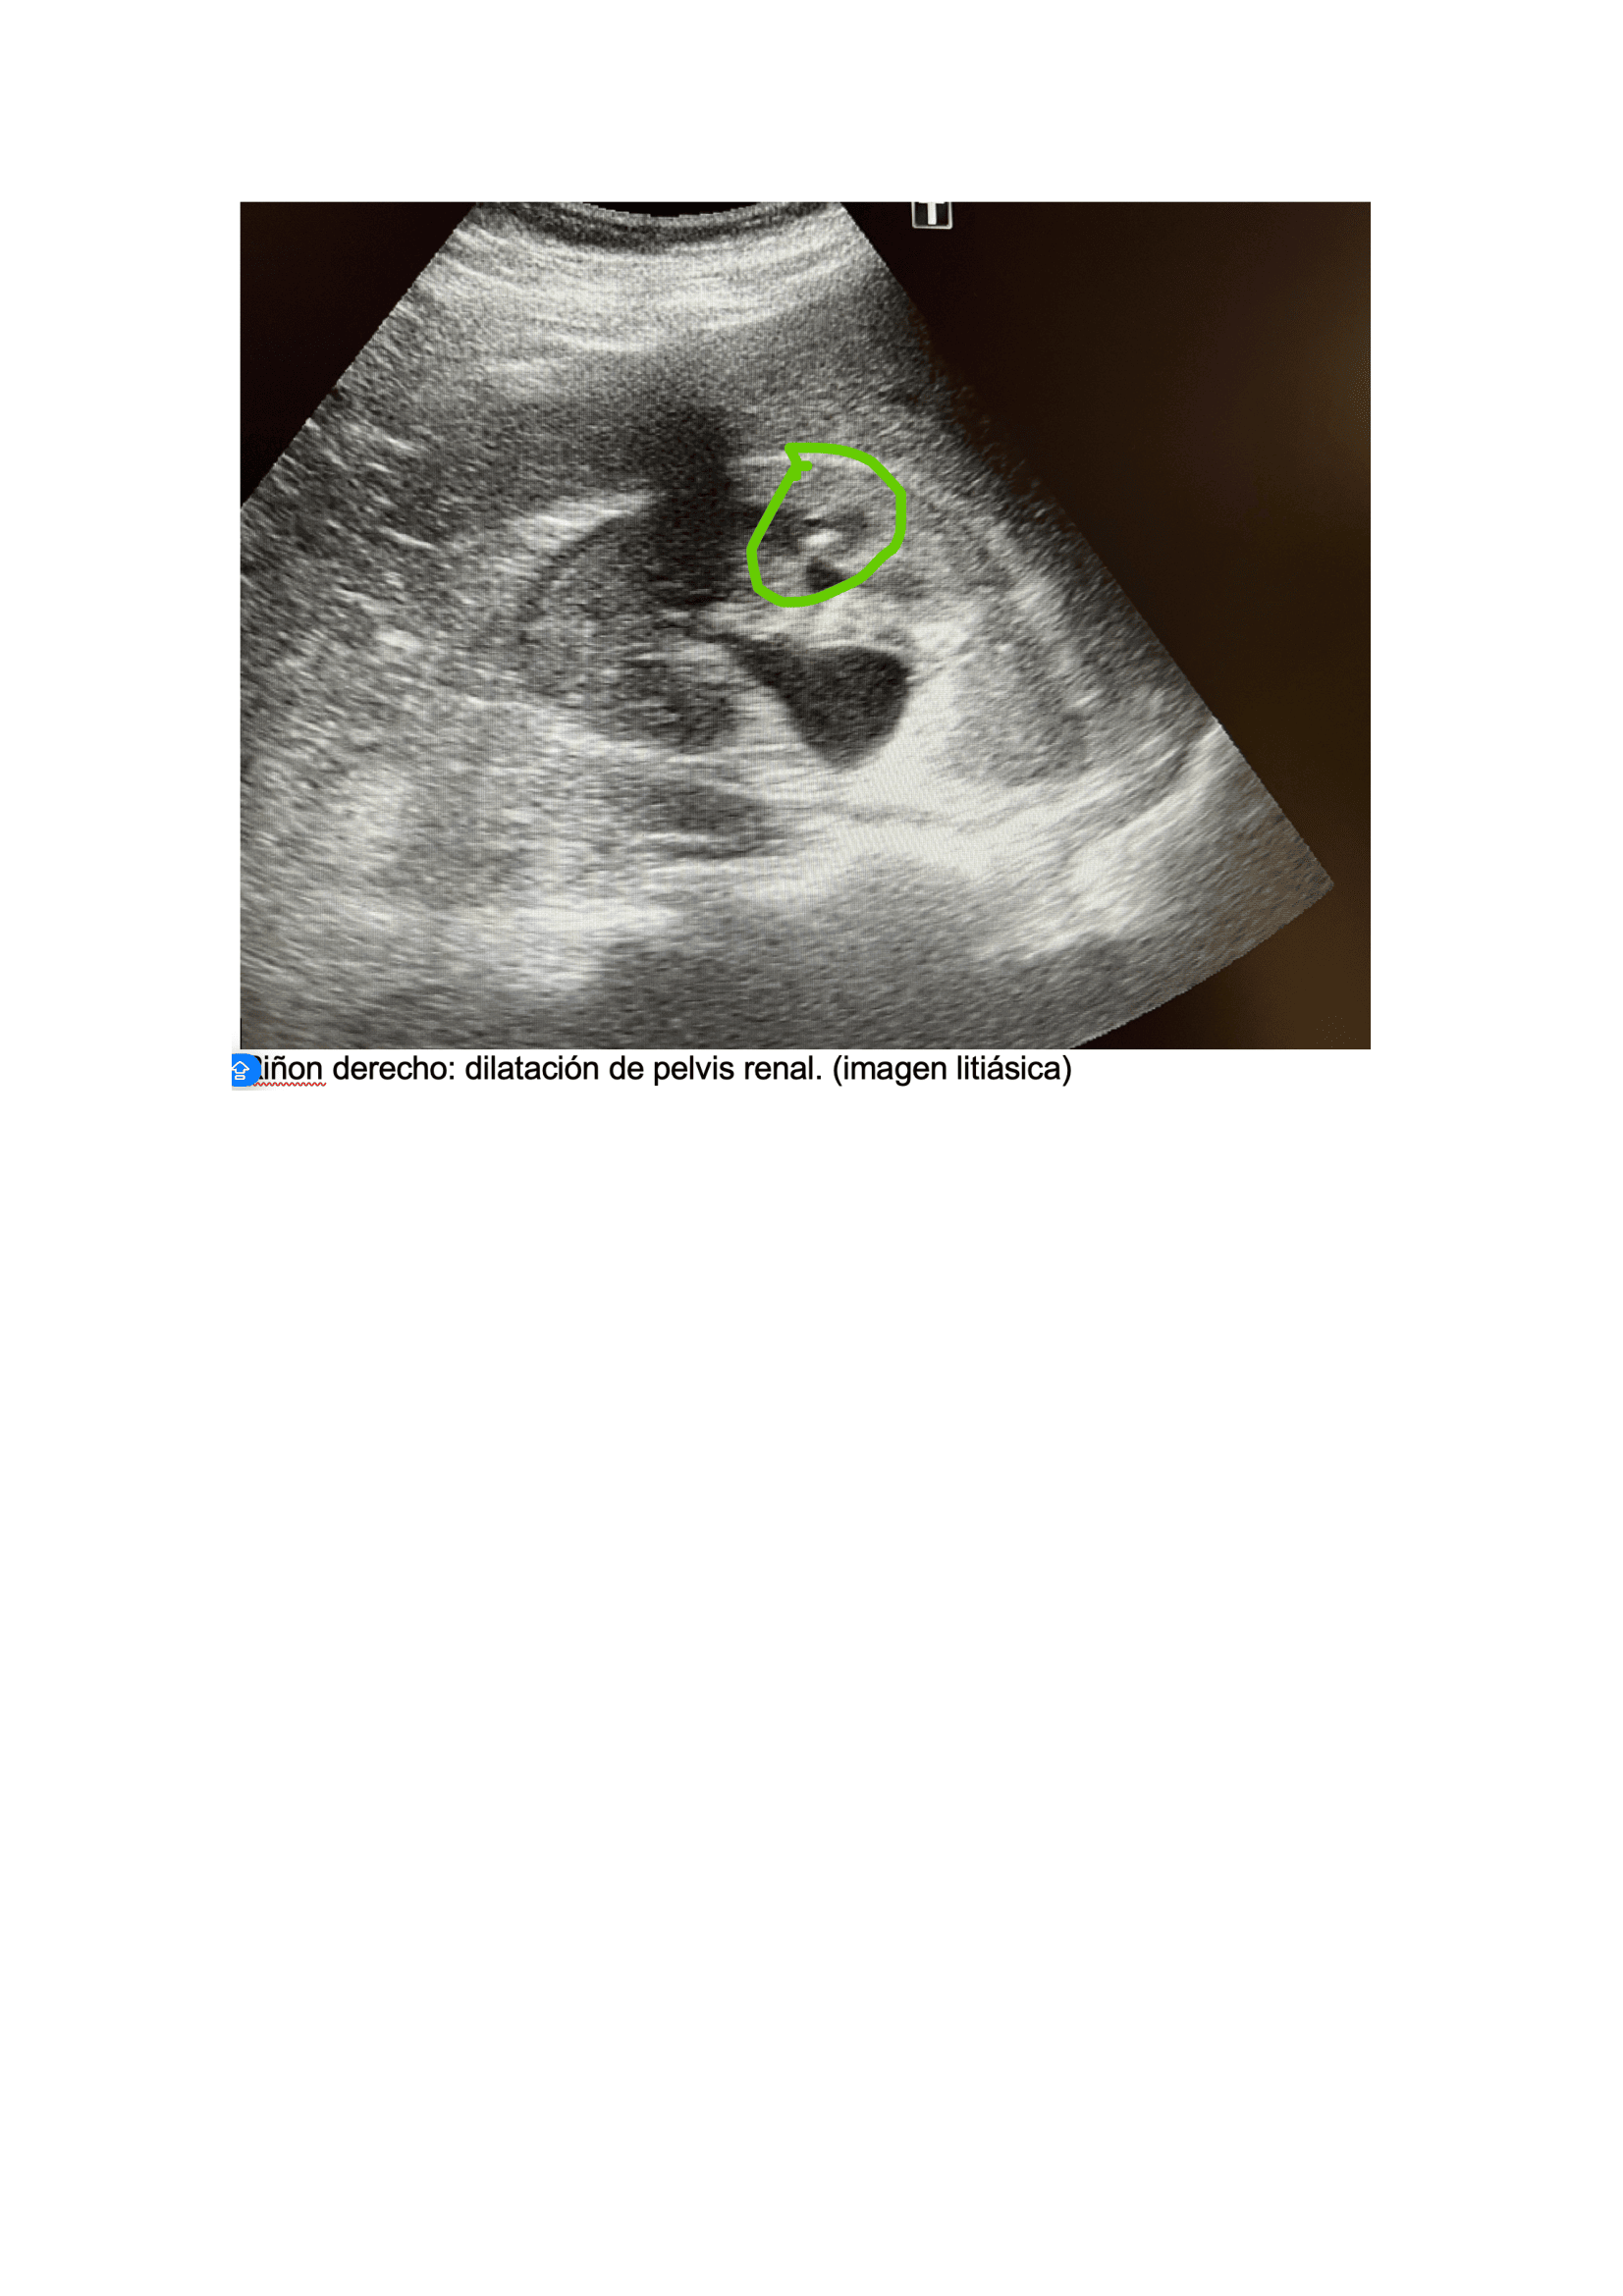

Urología: evidencia mejoría del cuadro clínico, niega fiebre, dolor. Refiere expulsión de pequeño cálculo tras 5 días de tratamiento. Ecografía, Riñón de tamaño normal, homogéneo, se evidencia imagen litiásica que deja sombra acústica posterior de 1,2 cm x 9 mm aprox. que no compromete vía urinaria, no dilatación de pelvis renal. Se deja tratamiento con tamsulosina durante 3 meses hasta nueva valoración. Control con su médico de familia, solicitar seguimiento de niveles ácido úrico y si alteración pautar tratamiento.